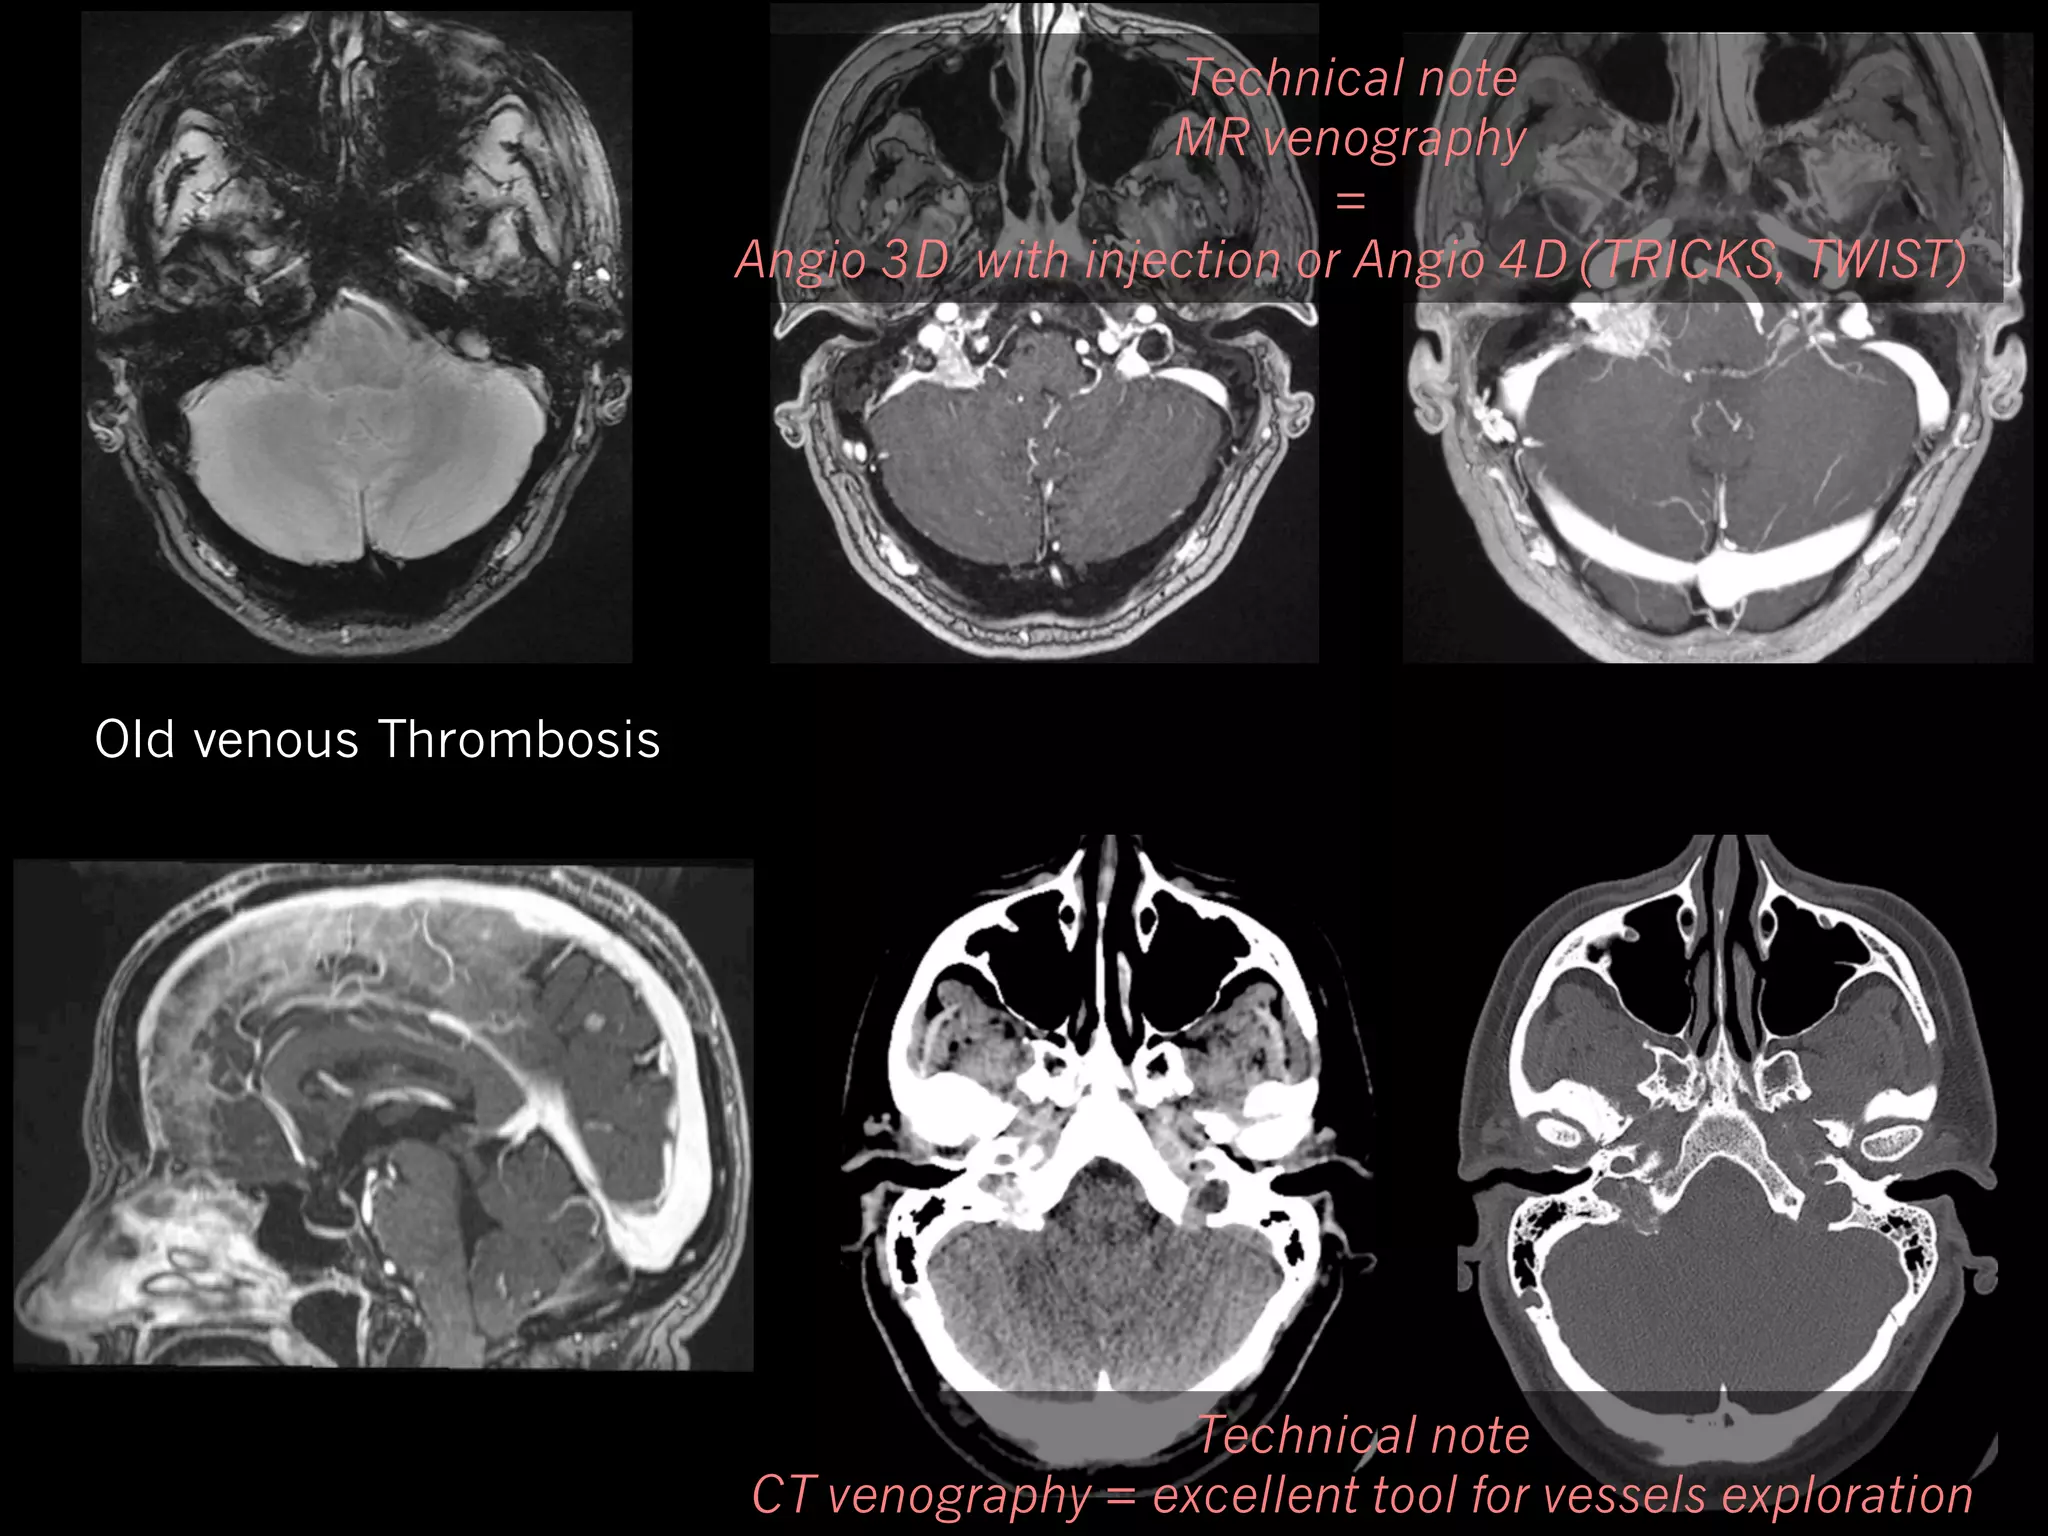

IIH and Veins

41 y.o woman. Headache. Bilateral pulsatile tinnitus.

Technical note

MR venography

=

Angio 3D with injection or Angio 4D (TRICKS, TWIST)

Old venous Thrombosis

CT venography = excellent tool for vessels exploration